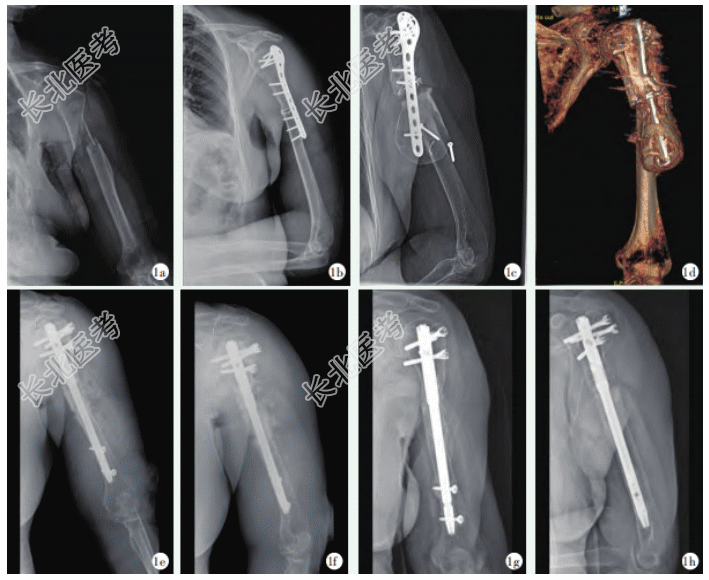

- [材料题] 患者女性,80岁,因“左上臂骨折术后9年,畸形、疼痛活动受限5年”为主诉入院。体格检查:患者左上臂中上段可见向前、向外突出畸形,周围可见多处陈旧性手术瘢痕,无明显渗出,左上肢肌肉萎缩明显,左上肢较右上肢短缩约2cm。左上臂中上段处压痛明显,压痛处可触及8cm×4cm肿物,质地硬,推之不移,未触及骨擦感及异常活动。左桡动脉搏动良好,左手各指血运、皮肤感觉及活动良好,未见垂腕、爪形手、猿手等异常症状,余肢体查体未见明显异常。患者既往因外伤致左肱骨干骨折,术前X线片示骨折类型为12-C型(图1a),在当地医疗机构行左肱骨骨折钢板内固定术+钢丝捆扎术。第1次术后X线片检查提示:左侧肱骨上段骨折内固定术后内固定器松脱、骨髓腔内密度增高(图1b);术后8年复查X线片均提示固定器松脱、骨折远端囊袋状异常密度影进行性增大、骨折断端无愈合倾向(图1c)。术后8年CT三维重建提示:左侧肱骨上段骨折内固定术后,骨折不愈合,金属内固定器下端松脱、左肱骨骨折远端前外侧囊袋状异常密度影(图1d)。患者多年来反复出现左上臂疼痛,左肩关节活动受限,近1年来上述症状再发加重,严重影响日常生活,于2022年8月以左肱骨骨不连收治于本院创伤骨科。结合病史、影像学及查体,符合左肱骨骨折术后骨不连并巨大包壳形成诊断,具备手术治疗指征。

排除禁忌证后行手术治疗。暴露骨折断端,检查骨折处可见断端对位差,骨折端硬化,近侧及远端骨质增生明显,远端形成类似假肱骨头的巨大包壳,内可见大量的大小约为0.3cm×0.3cm的白色圆球状颗粒。用咬骨钳清除断端之间的瘢痕肉芽组织,去除不规则状骨质、远端增生骨质,直至渗血为止,留取白色圆球状颗粒送病理检查;使用骨折复位钳使断端重新对位,开槽扩髓,置入髓内钉固定,远近端各拧入2枚螺钉,被动活动上臂见骨折断端无微动,透视下复位满意后冲洗术口,植入同种异体骨及骨修复材料后关闭切口,术毕(图1e,1f)。术后1年复查X线提示骨折断端对线对位好,骨质密度增高、骨痂形成(图1g,1h)。